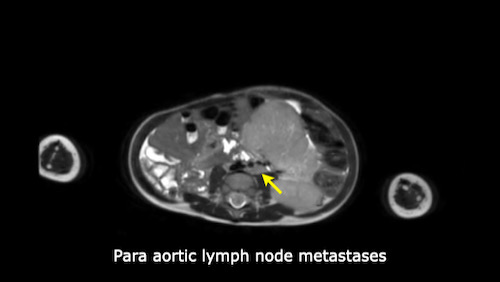

Left sided nephroblastoma in a two-year-old girl. Note the para-aortal lymph node metastasis (arrow).

Khi bạn đã xác định chắc chắn nguồn gốc thận của khối u, hãy khảo sát thận còn lại để tìm khối u hoặc bệnh lý nephroblastomatosis (xem bên dưới).

Tìm kiếm các hạch bạch huyết cạnh động mạch chủ bị phì đại.